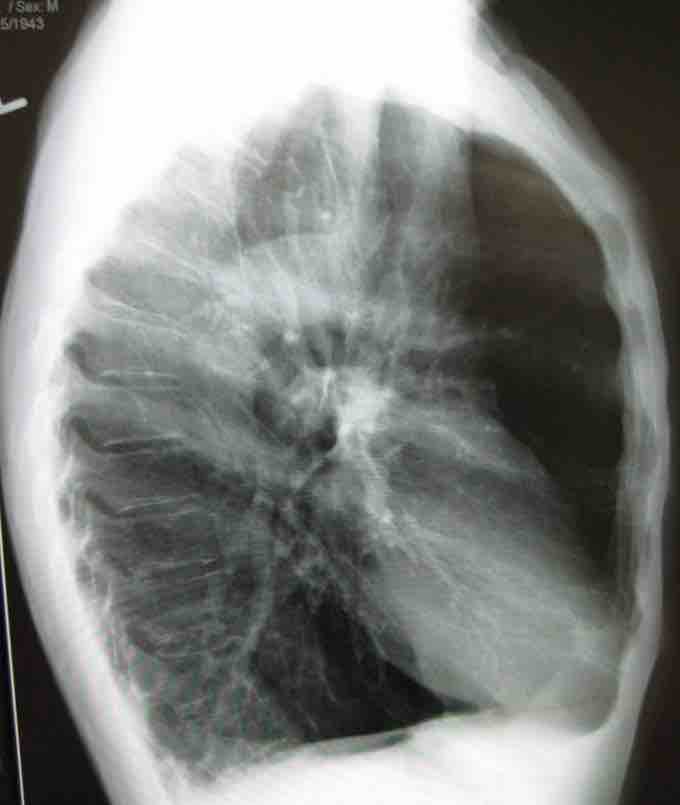

Lateral chest X-ray of a patient with emphysema

Emphysema is a common lung disease in the elderly. Note the barrel-shaped chest and flat diaphragm.